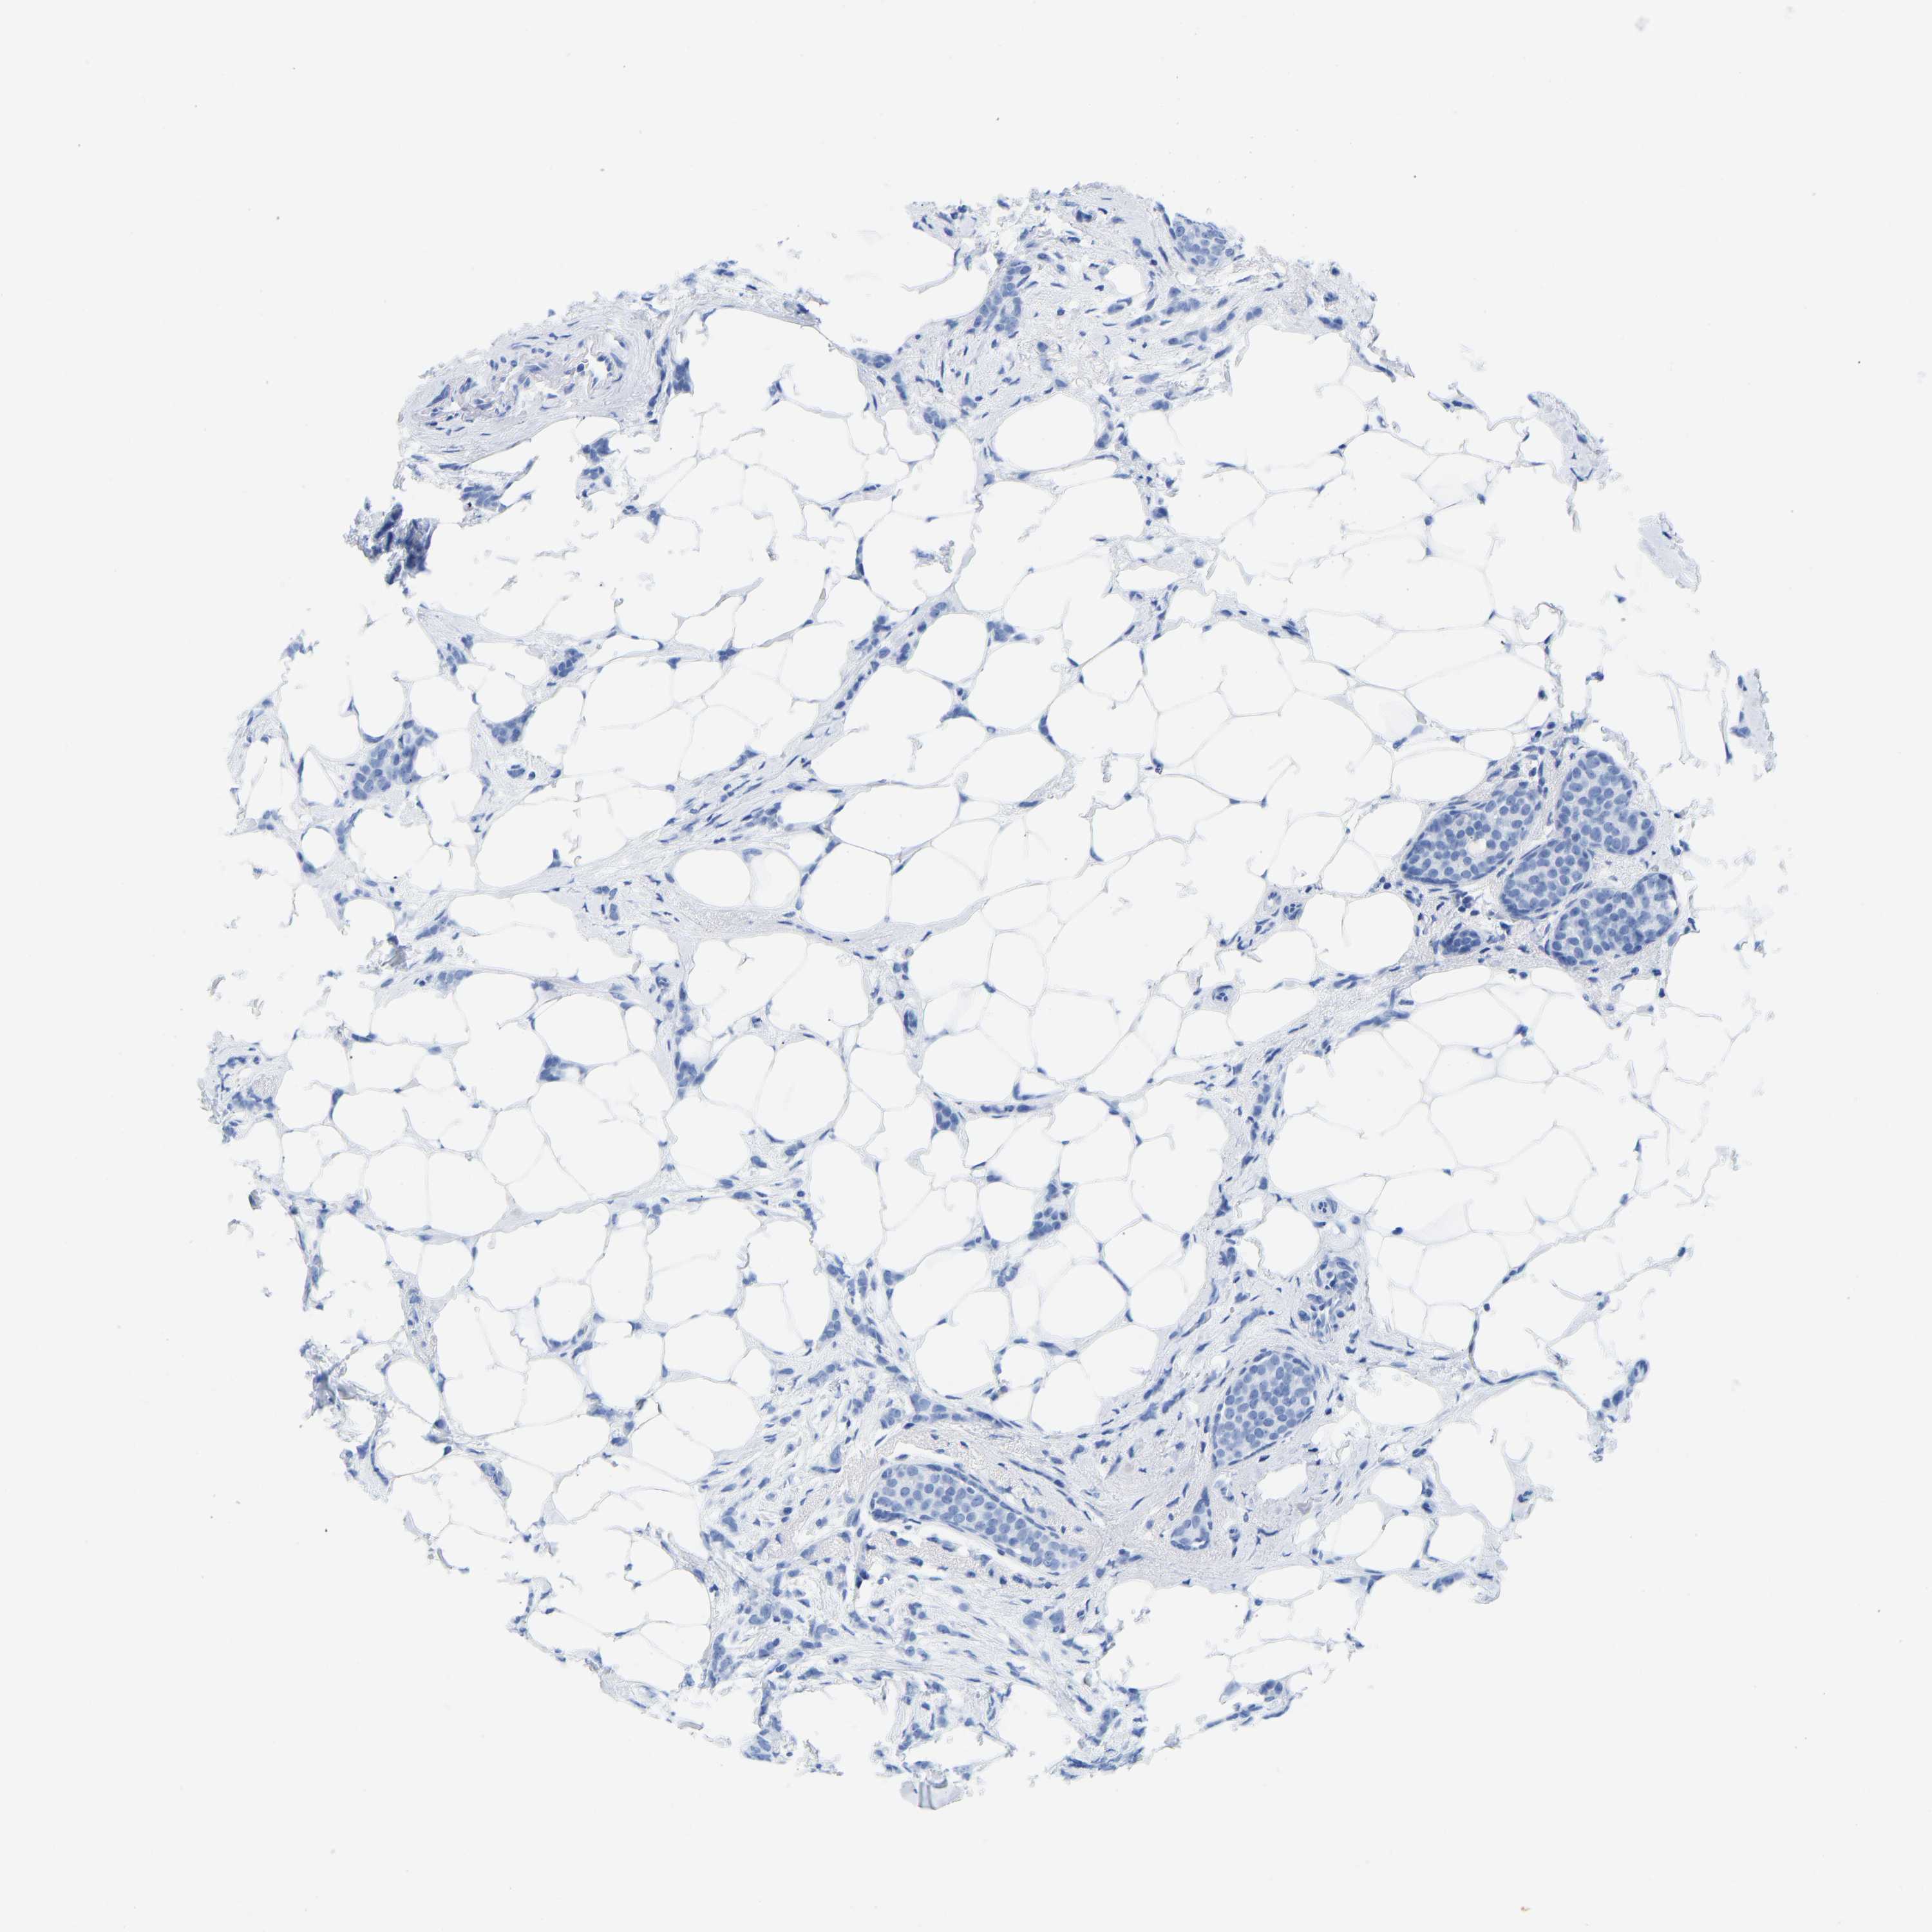

CANCER BREAST CANCER Show tissue menu

BRCA TCGA BRCA VALIDATION PROTEIN EXPRESSION